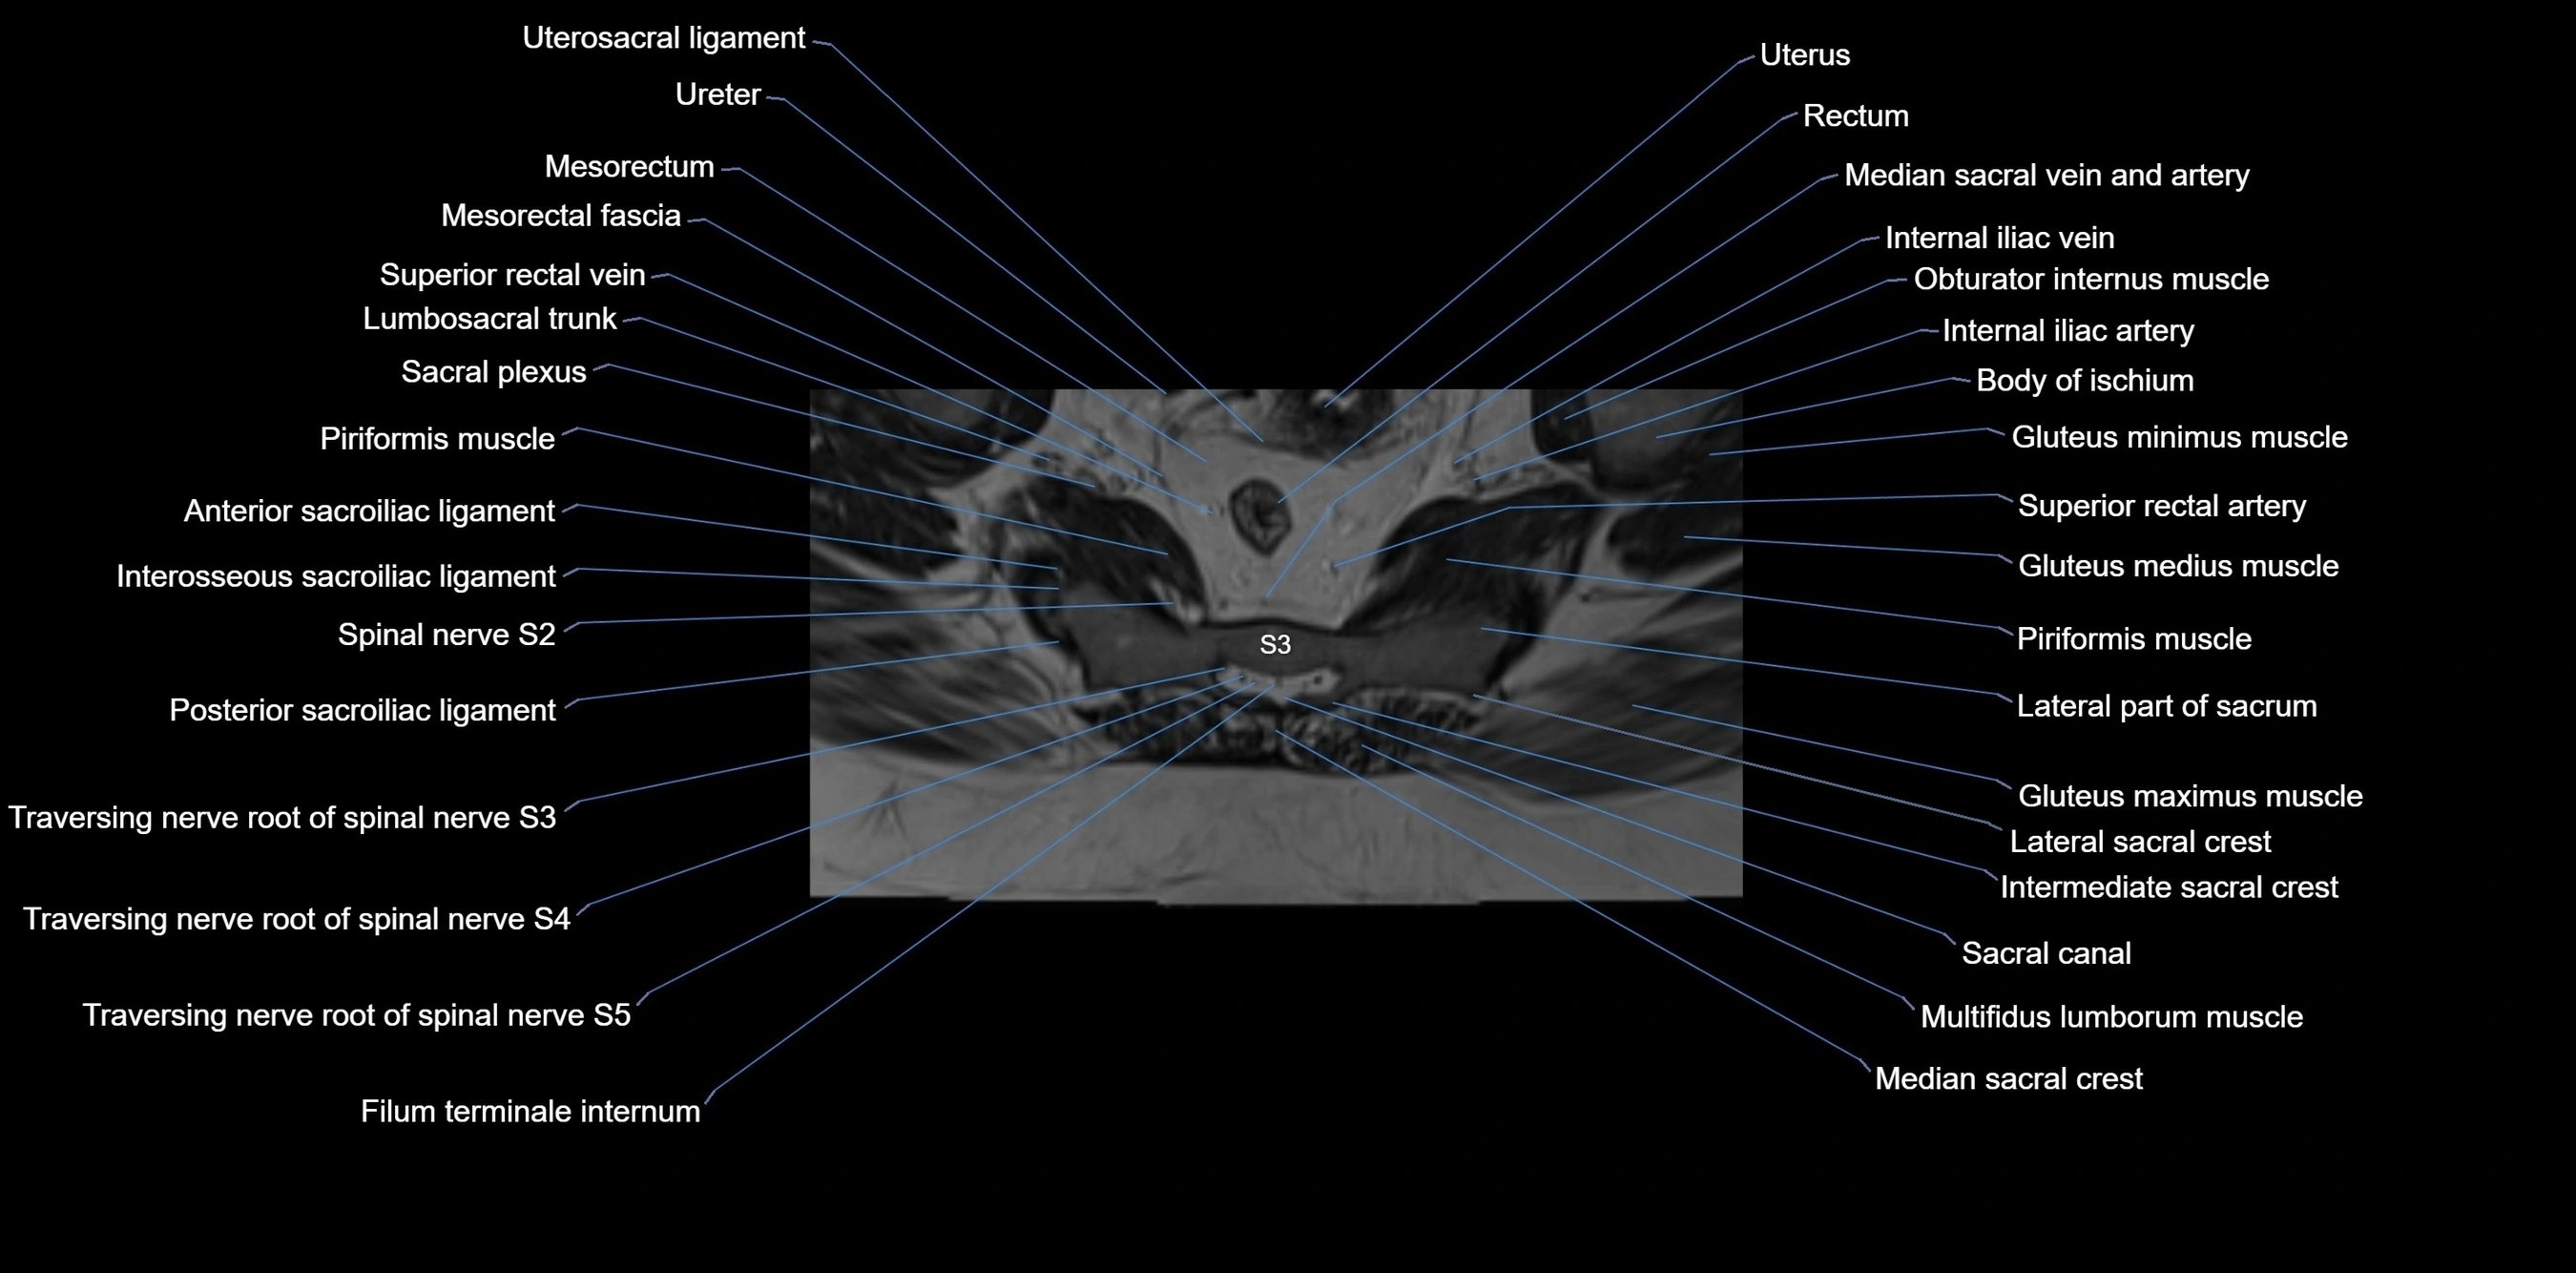

MRI image

image